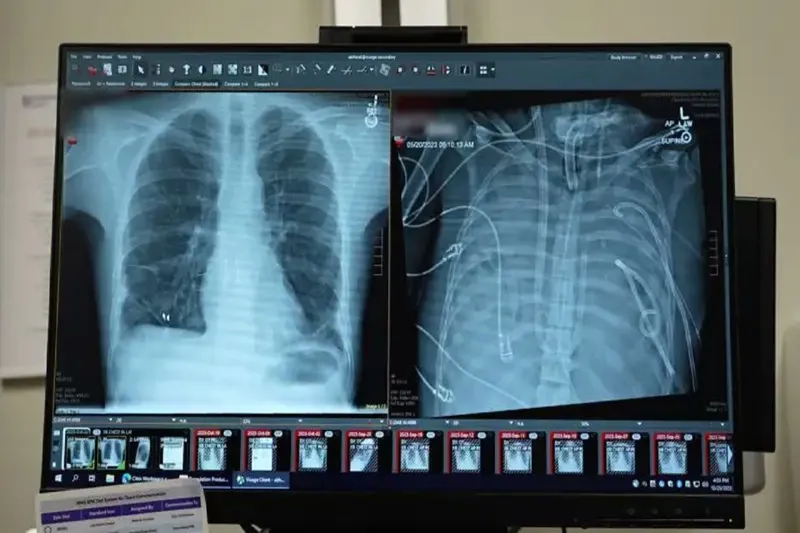

Olay, 2023 yılında Missouri eyaletinin St. Louis kentinde yaşayan 33 yaşındaki bir erkeğin influenza B virüsüne yakalanmasıyla başladı. Hastaneye kaldırılan hastaya, antibiyotiklere dirençli Pseudomonas aeruginosa bakterisinin neden olduğu ikinci bir enfeksiyon daha bulaştı. Enfeksiyon kana yayıldı ve bağışıklık sisteminin aşırı tepkisiyle birlikte akciğerler işlevini yitirdi.

Bunun üzerine cerrahlar, hastanın hastalıklı akciğerlerini tamamen çıkararak geliştirdikleri yapay akciğer sistemine bağladı. Sistem, kalbin sağ tarafından alınan kanı bir pompadan geçirerek oksijen ekliyor ve karbondioksiti uzaklaştırıyor, ardından kanı kalbin sol tarafına yönlendirerek vücuda pompalanmasını sağlıyor. Böylece hem kalbin normal işlevi korunuyor hem de dokulara oksijen ulaştırılıyor.

Daha önce doktorlar, ekstrakorporeal membran oksijenasyonu (ECMO) adı verilen dış destek sistemini kullanarak, nakil bekleyen bazı hastaları akciğersiz olarak hayatta tutmuştu. Ancak Bharat, ECMO’nun kalp için yeterli kan akışını sağlamadığı için gerçek anlamda bir yapay akciğer olmadığını ifade etti.